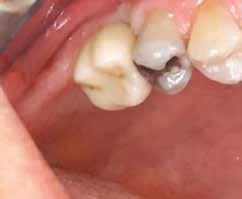

1. ábra: A műtét előtti szituáció, megfigyelhető az implantátumok közötti konkáv terület, ahova könnyen beragad az ételmaradék, és könnyen kialakul a periimplantitis.

Egy 47 éves páciens jelentkezett nálunk egy alsó, hátsó foghiánnyal, ahol jelentős csontfelszívódást tapasztaltunk a moláris fogak korábbi eltávolítása miatt (1. ábra). Két implantátum körül is volt ínyrecesszió, illetve a keratinizált íny mennyisége minimális volt (kevesebb, mint 1 mm). 4 hónappal az implantációt követően ínykorrekciót végeztünk.